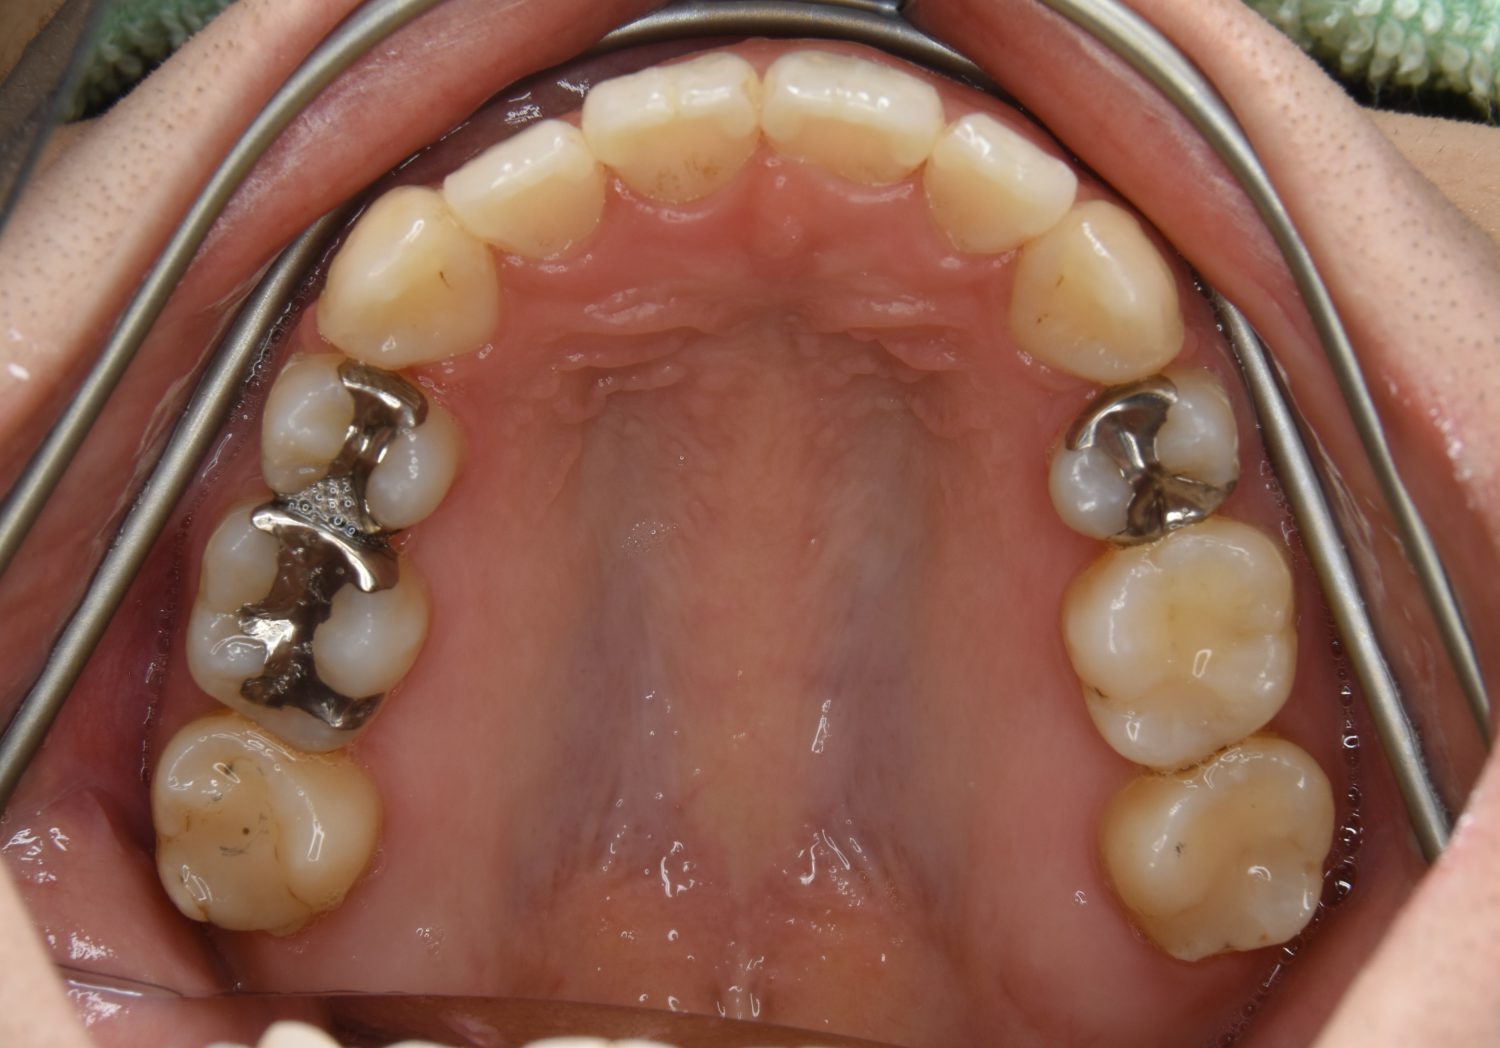

前歯部開咬の症例紹介①

Before

主訴

前歯が開いているのが気になる。

治療内容

上リンガルブラケット(舌側装置)、下ラビアルブラケット(唇側装置)に矯正用アンカースクリューを併用し非抜歯で治療を行いました。

治療費

1,200,000 円(税込)

治療期間

33ヶ月

通院回数

34回

想定されたリスク

※歯根吸収、歯肉退縮、歯髄壊死、顎関節症状

上下の前歯が開いており前歯では全く噛めていない状態でした。臼歯の圧下を行うことで前歯でも咬合できるようになり機能面のみでなく審美面も著しく改善しました。